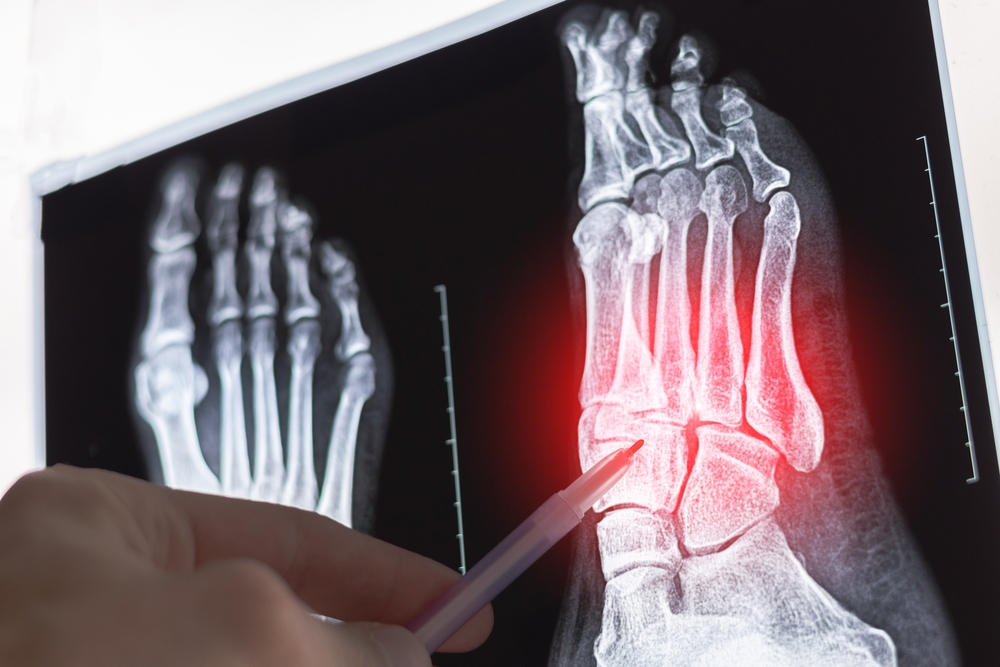

Diagnozavimui gydytojas apžiūri jūsų pėdą, įvertina simptomus ir išklauso skundus. Kad būtų tiksliau nustatyta diagnozė, dažnai prašoma atlikti rentgeno nuotrauką – taip išvengiama lūžių ar kitų galimų pažeidimų. Jei reikia, papildomai atliekamas ultragarsinis arba magnetinio rezonanso tyrimas, ypač jei įtariami minkštųjų audinių pažeidimai.